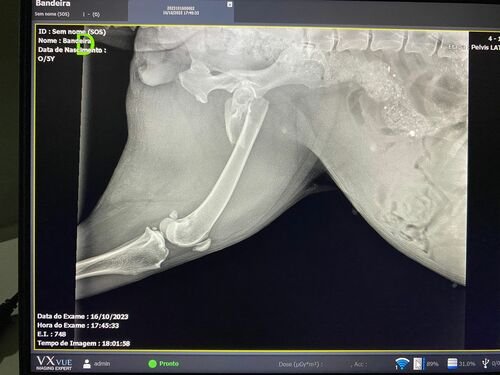

Sou Laís Dotta, e em setembro fiz vários anúncios com o meu irmão em busca da nossa cachorra Pandora uma rottweiler linda e mto amada que fugiu no sítio dia 15/09/2023, infelizmente até hj ainda não a encontramos, mas no meio do caminho dessa busca nos apareceu a Athena (nome dado a cachorra pela minha mãe) uma cachorra aparentemente mto sofrida, e não conseguimos deixar-la para trás sem a resgatar para ajuda lá, pois ela estava machucada, meu irmão a levou no hospital público, aí veio a notícia que a perna estava fraturada e ela ia ter que fazer uma cirurgia, mas infelizmente essa cirurgia era 4 mil reais e eles não conseguiram a cirurgia para ela, a devolveram pro meu irmão, assim desde então ela está sendo cuidada na casa da minha mãe a base de medicamentos e amor, mas Deus guiou minha mãe ao lugar certo, e conseguimos uma “caridade” para operar a Athena por $1600,00 , onde ainda infelizmente não temos esse dinheiro, pois já gastamos mto com ela e depois da cirurgia ainda vão ter mtos outros medicamentos…… então hj com ideia de amigos estamos aqui para pedir a vcs uma ajuda para salvar essa guerreira linda…..